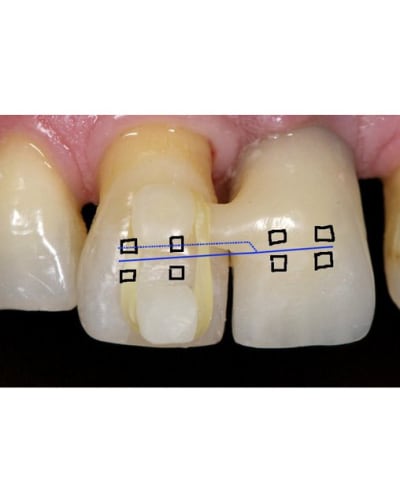

Le probllème que tu a en ortho habituellement c'est la force de reaction, donc quand tu veux bouger une dents pour limiter ces effets tu es obliger de prendre appuis sur plusieurs dents.

La tu utilise un implant donc pas besoin de se soucier de la force de réaction. L'implant il ne va pas bouger. Donc un système avec deux brackets et parfaitement gérable au niveau mécanique.

Pour ingresser la dent tu fait juste un pliage du type sur le dessins.

SI la dent procline tu plie le fil en lingual.

Par contre attention vue qu'il s''agit d'un intrusion sur un terrain paro je dirais qu'il ne faut utiliser que des fils de faible diamètre car il ne doivent surtout pas remplir le slot.

Ici il y aurait une très bonne indication pour des danchemon.

Normalement tu dois tout pouvoir faire avec un Niti 0.014.

Ps : sur le shema j'ai mis les bracket en vestibulaire mais il n'y a strictement aucun problème pour les mettre en lingual, mis a part que le pliage devient beaucoup plus délicat.

Mais le gros avantage de coller en lingual ici serait de faire passer la ligne d'action de la force ingressive plus proche du centre de résistance de la 11 et donc de diminuer voir supprimer complètement le mouvement parasite de vestibulo version.

Avec un appuis sur un implant et deux bracket tout devient beaucoup plus simple. Si la dent procline un peut c'est facile a corriger en donnant une pliure en linguale.

Vue qu'un des points d'appuis est immobile le seul élément qui peut bouger c'est la 11 donc très facile de contrôler la position par pliage.

Le problème en lingual c'est que le pliage du fil est plus délicat car on ne peut pas vraiment travailler en vision direct.